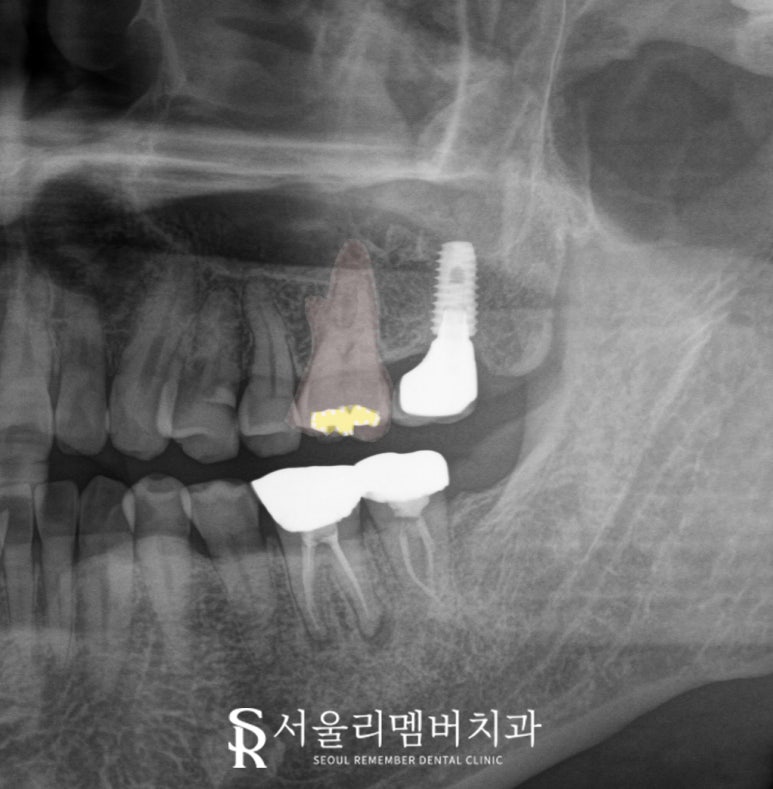

왼쪽 위 첫 번째 큰 어금니를 보겠습니다.

2025.01.27

이 치아는 음식을 먹을 때마다

시큰시큰하거나 찌릿한 느낌을 준다 합니다.

이것은 전형적인

크랙의 증상이며

crack syndrome으로

평가하는데 좋은 지표가 됩니다.

문제는 엑스레이를 찍어도

그 크랙이 미세해서

명확히 보이지 않는다는 점인데요,